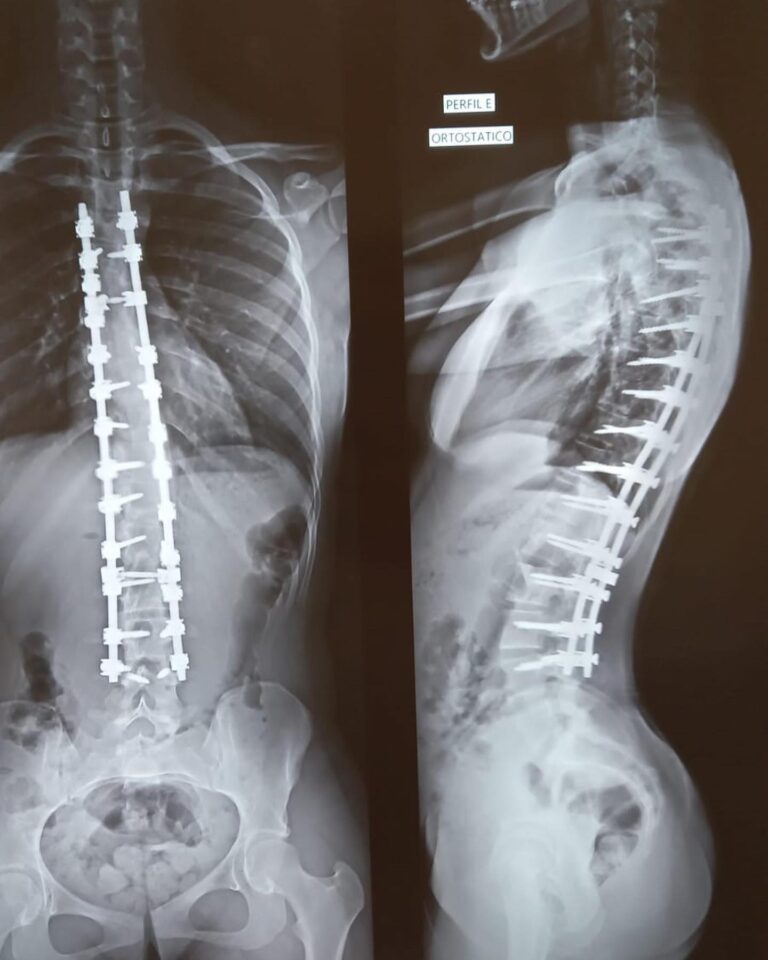

A cirurgia minimamente invasiva na coluna vertebral é um tipo de cirurgia que usa técnicas avançadas e instrumentação especializada para operar com mínima perturbação aos tecidos circundantes.

Pacientes com dores crônicas na coluna que não respondem a tratamentos conservadores, aqueles com discos herniados, estenose espinhal, fraturas vertebrais e algumas deformidades da coluna podem ser candidatos à cirurgia minimamente invasiva.

As taxas de sucesso variam dependendo da condição que está sendo tratada. No entanto, em geral, a cirurgia minimamente invasiva na coluna tem taxas de sucesso comparáveis, se não superiores, às dos procedimentos abertos tradicionais para muitas condições.